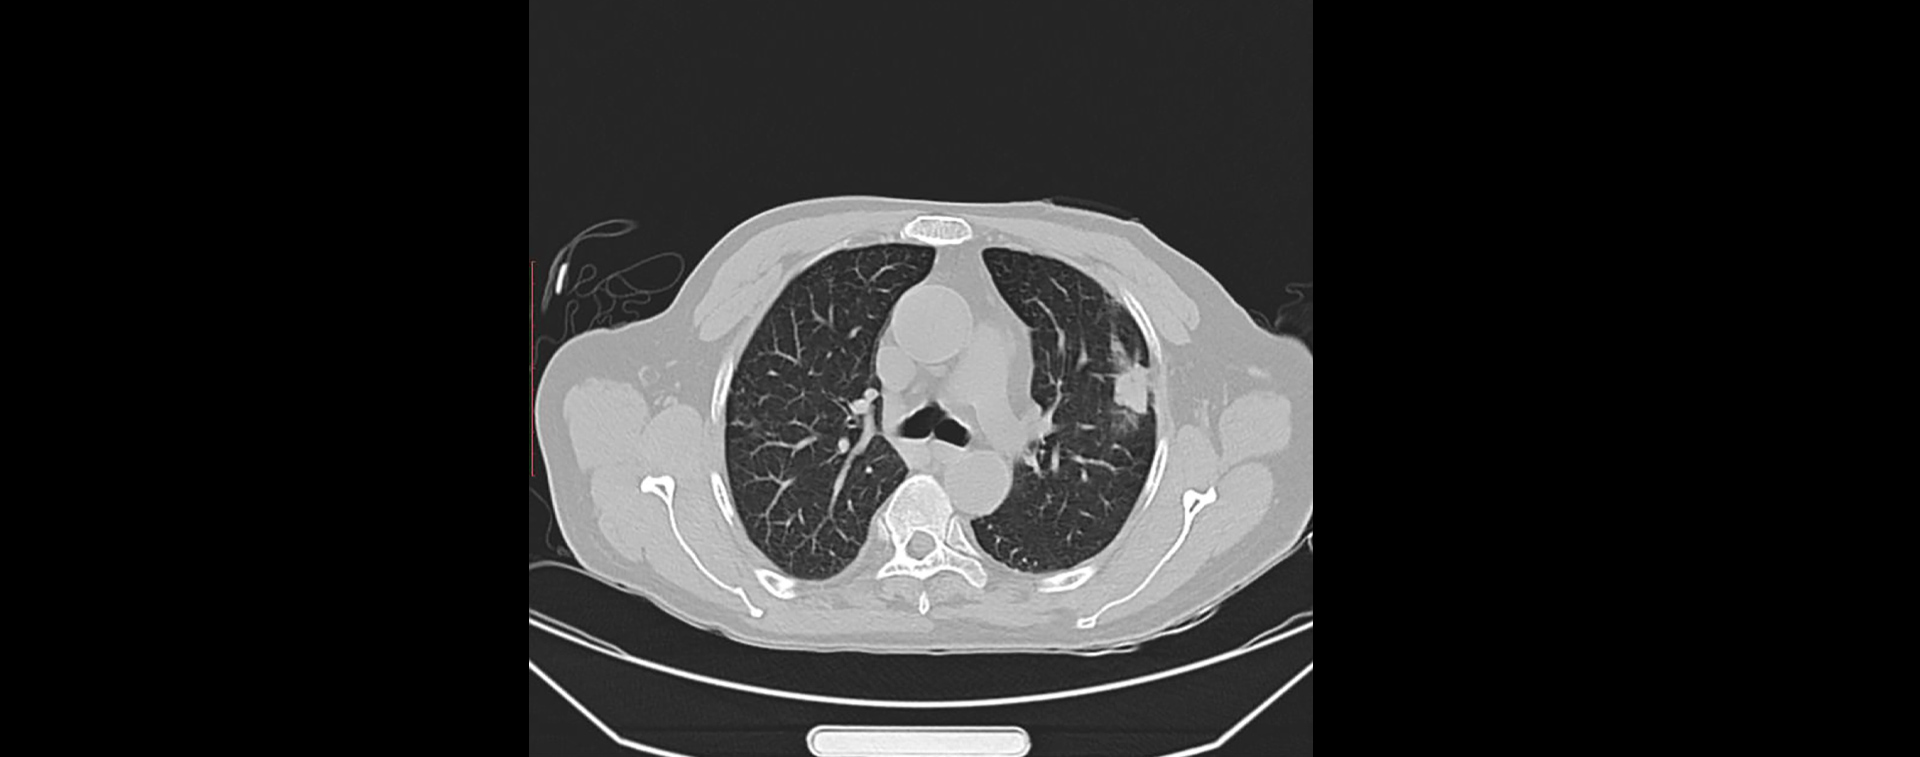

肺结节穿刺活检

患者体检中发现左肺上叶靠胸壁有一结节,需穿刺活检确定良恶性。

1)患者在仰卧位下平扫,通过断层图配合定位栅格确定下针位置、角度和深度(图1);

2)下针后扫描监测穿刺针位置,并测出距离靶向位置的距离和角度;

3)根据测量值调整下针长度和角度,避开血管、骨骼和神经等结构,穿刺针尖进入结节中心位置(图2);

4)更新穿刺枪芯,剪切取出活检组织用95%乙醇标本瓶保存;

5)取出穿刺针后再次行CT肺部平扫,确定无气胸及出血等并发症(图3)。

图1

图2

图3